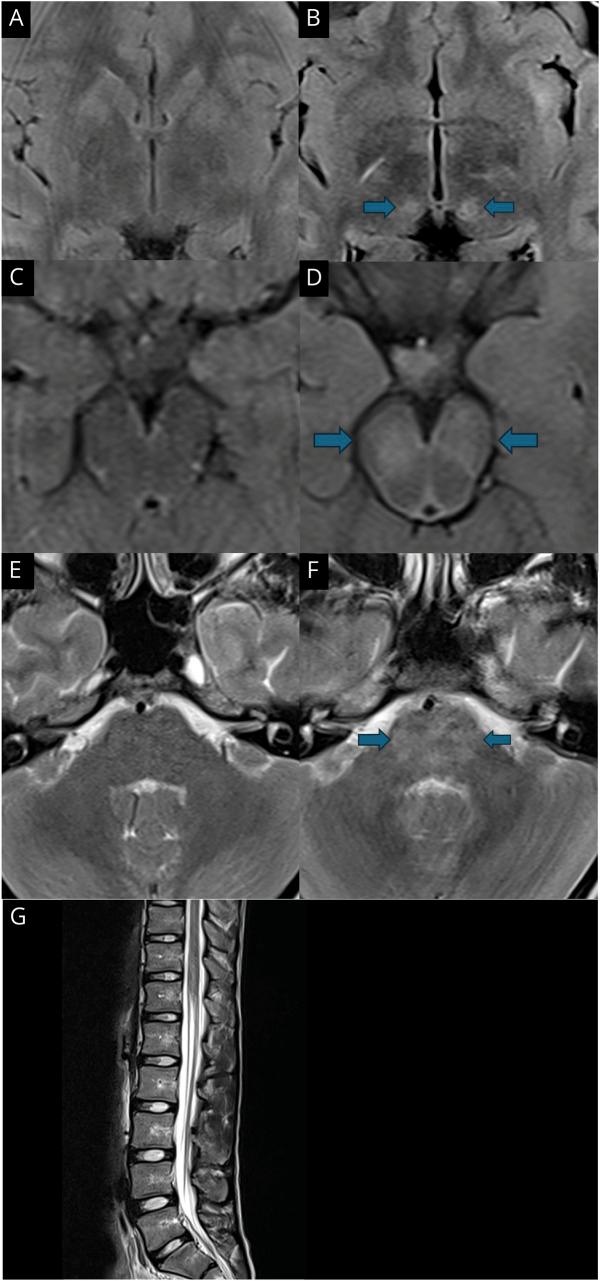

We identified and included 15 children (5 girls, 10 boys). The median age at onset was 9.9 years (range: 2-16 years). All children presented with features of AE or meningitis, acute cerebellitis, or transverse myelitis. CSF pleocytosis was common (13/15, median 245 cells/μL), and 13 (87%) of 15 harbored GFAP-abs in their CSF, 8 (53%) of whom did not have detectable GFAP-abs in their serum. MRI was abnormal in 15 (100%) of 15 children: Specific patterns included confluent lesions in the pons or caudate nucleus (11/15; 73%), peri-aqueductal regions (13/15; 87%), and spinal cord (6/10; 60%). 12 children had a favorable outcome (mRS score of </= 1). Two patients died in the acute phase or during follow-up.

我们确定并纳入了 15 名儿童(5 名女孩,10 名男孩)。发病中位年龄为 9.9 岁(范围:2-16 岁)。所有患儿均表现为 AE 或脑膜炎、急性小脑炎或横贯性脊髓炎的特征。CSF 细胞增多症常见(13/15,中位数 245 个/μL),15 名患儿中有 13 名(87%)的 CSF 中存在 GFAP-abs,其中 8 名(53%)患儿血清中未检测到 GFAP-abs。15 名患儿的 MRI 异常(100%):特定模式包括桥脑或尾状核的融合性病变(11/15;73%)、导水管周围区域(13/15;87%)和脊髓(6/10;60%)。12 名患儿预后良好(mRS 评分<=1)。2 名患儿在急性期或随访期间死亡。